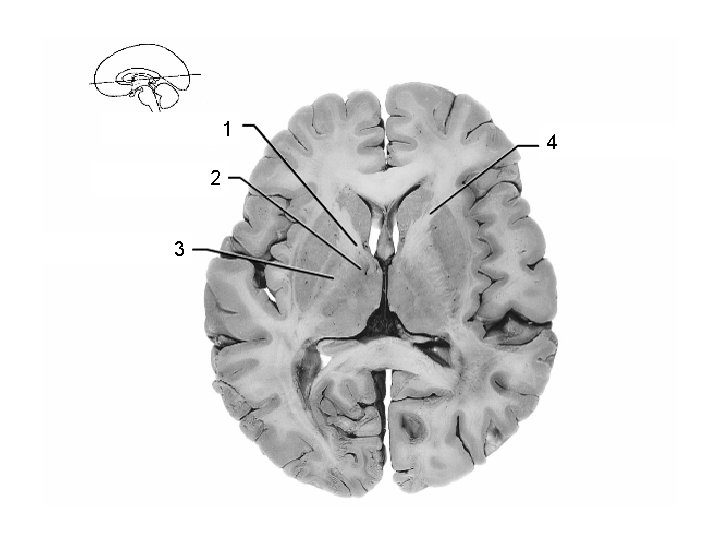

1 Thalamus 2 3 Lentiform Nucleus

1 2 Putamen 3 (lentiform nucleus)

Post. limb, int. capsule: corticospinal + corticopontine 2 + thalamocortical fibers Body 3 of lateral ventricle thalamus 4 descending cortical 1 fibers in crus cerebri of midbrain 5 Ventricle III Lentiform nucleus 6 putamen is visible) (only